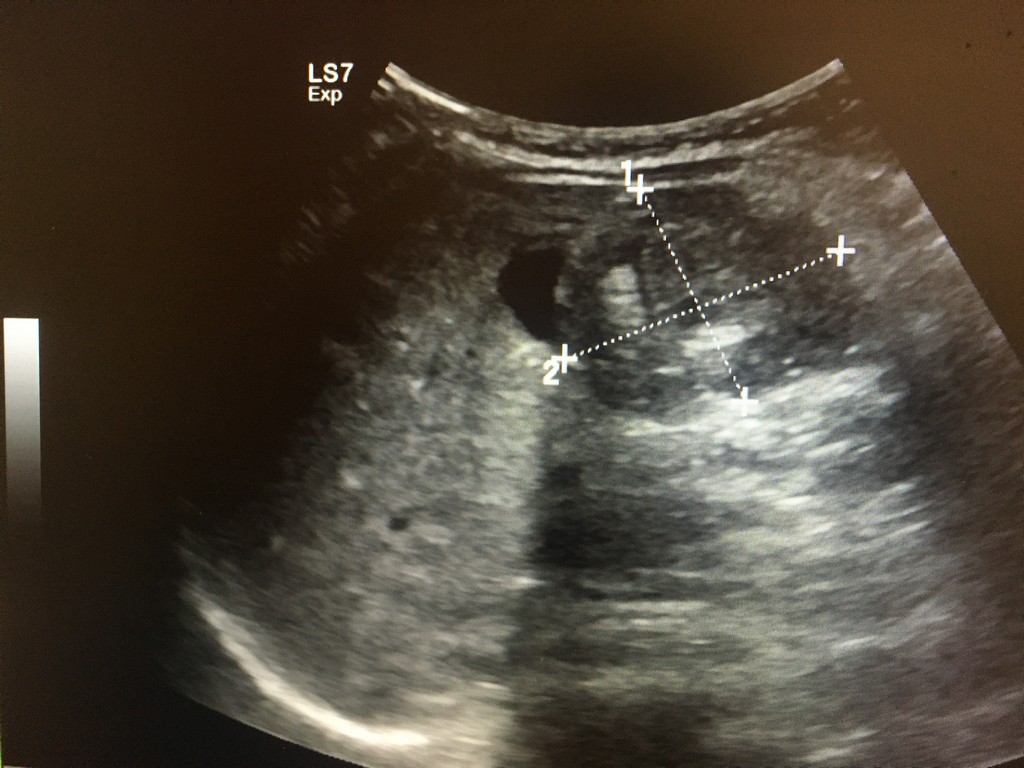

小兒腸胃科張雲傑醫師立即做腹部超音波檢查,發現「腸套疊」後立即以超音波搭配生理食鹽水灌腸,做腸套疊復位術。